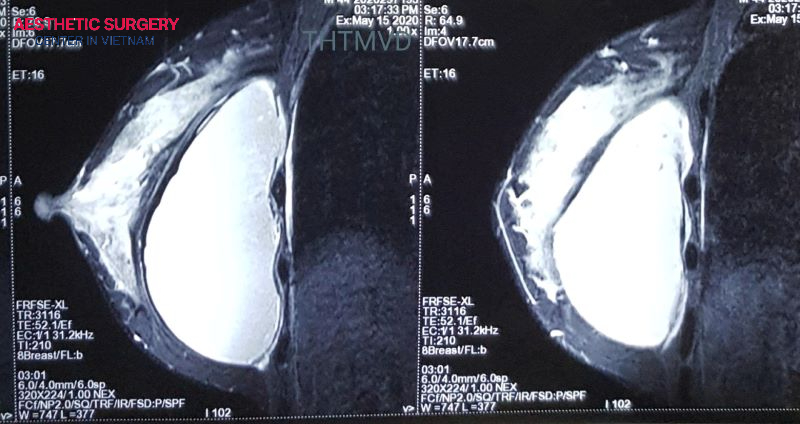

However, for patients with modern cohesive silicone implants, a rupture may leak silently without visible external signs. Therefore, to detect potential issues, patients should undergo regular monitoring with MRI or ultrasound starting 5–6 years after implantation.

Regular MRI/X-ray screening

Before breast augmentation, patients should undergo X-ray or ultrasound to assess breast tissue health and rule out conditions such as cysts or infections. After silicone implant surgery, doctors typically recommend periodic MRI scans every 2–3 years to detect silent leaks or implant ruptures early, allowing timely intervention.